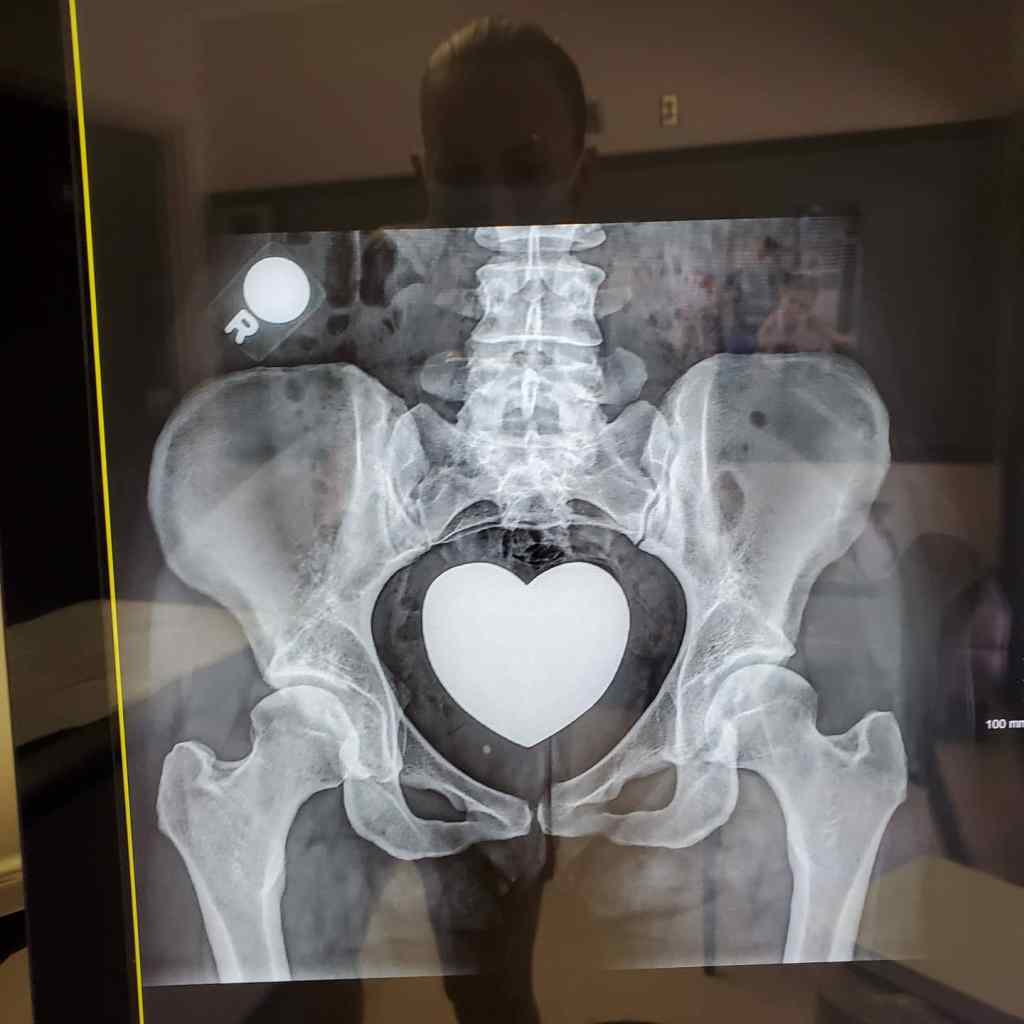

My happy Xray image doesn’t show too much to the untrained eye, but my hip map from my CT shows A LOT. The center edge angle is at 26 degrees, which is right at the cusp of where they would like it to be during surgery. They used to go off of this number for arthroscopy (explained later), and I would have been within the green years ago. But, they started noticing that some people relapsed and would once again damage their labrum. They started looking at other reasons and other angles during surgery consideration — the Tonnis angle and the acetabular coverage. The Tonnis angle shows the roof coverage so to speak of my ball head. For them to do arthroscopic surgery without the PAO (also explained later), I would need to be at 10 degrees or lower. They say 10-12 degrees would be pushing it and that most people in that range end up damaging their labrum again. My number degree… is 17. Yikes! They would NEVER consider surgery for my tear without the PAO. And my acetabular coverage is way under what they would consider as satisfactory. As a dancer, it gives me more flexibility but much less stability.